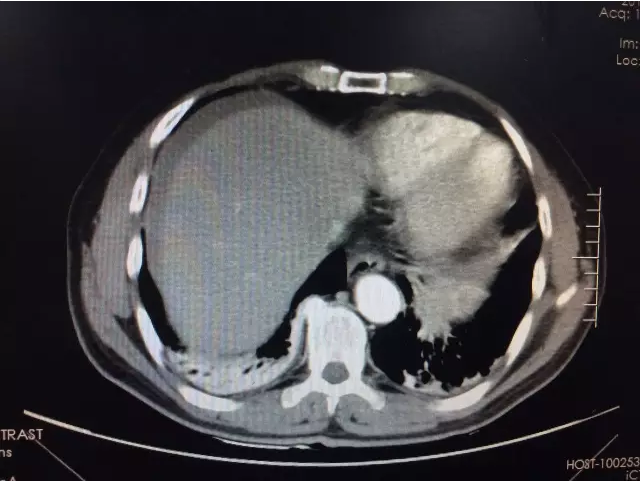

科主任崔小兵主任医师诊视患者后指出:“诊断考虑胃大弯占位:间质瘤可能,目前患者腹痛剧烈,有腹膜炎体征,不排除有肿瘤破裂可能,急查腹部CT,完善相关化验检查,尽早手术。”紧急动员之后,管床医生及护士密切合作,启动急危重症患者工作流程,全程陪同外出检查,结果提示:1.胃巨大占位;2.盆腹腔大量积液,考虑胃间质瘤破裂;3.失血性休克代偿期(患者心率102次/分,血压105/74mmHg)。主任当机立断,要求紧急联系麻醉科、输血科,拟于假期前一天急诊手术探查。

术前CT提示肝周积液